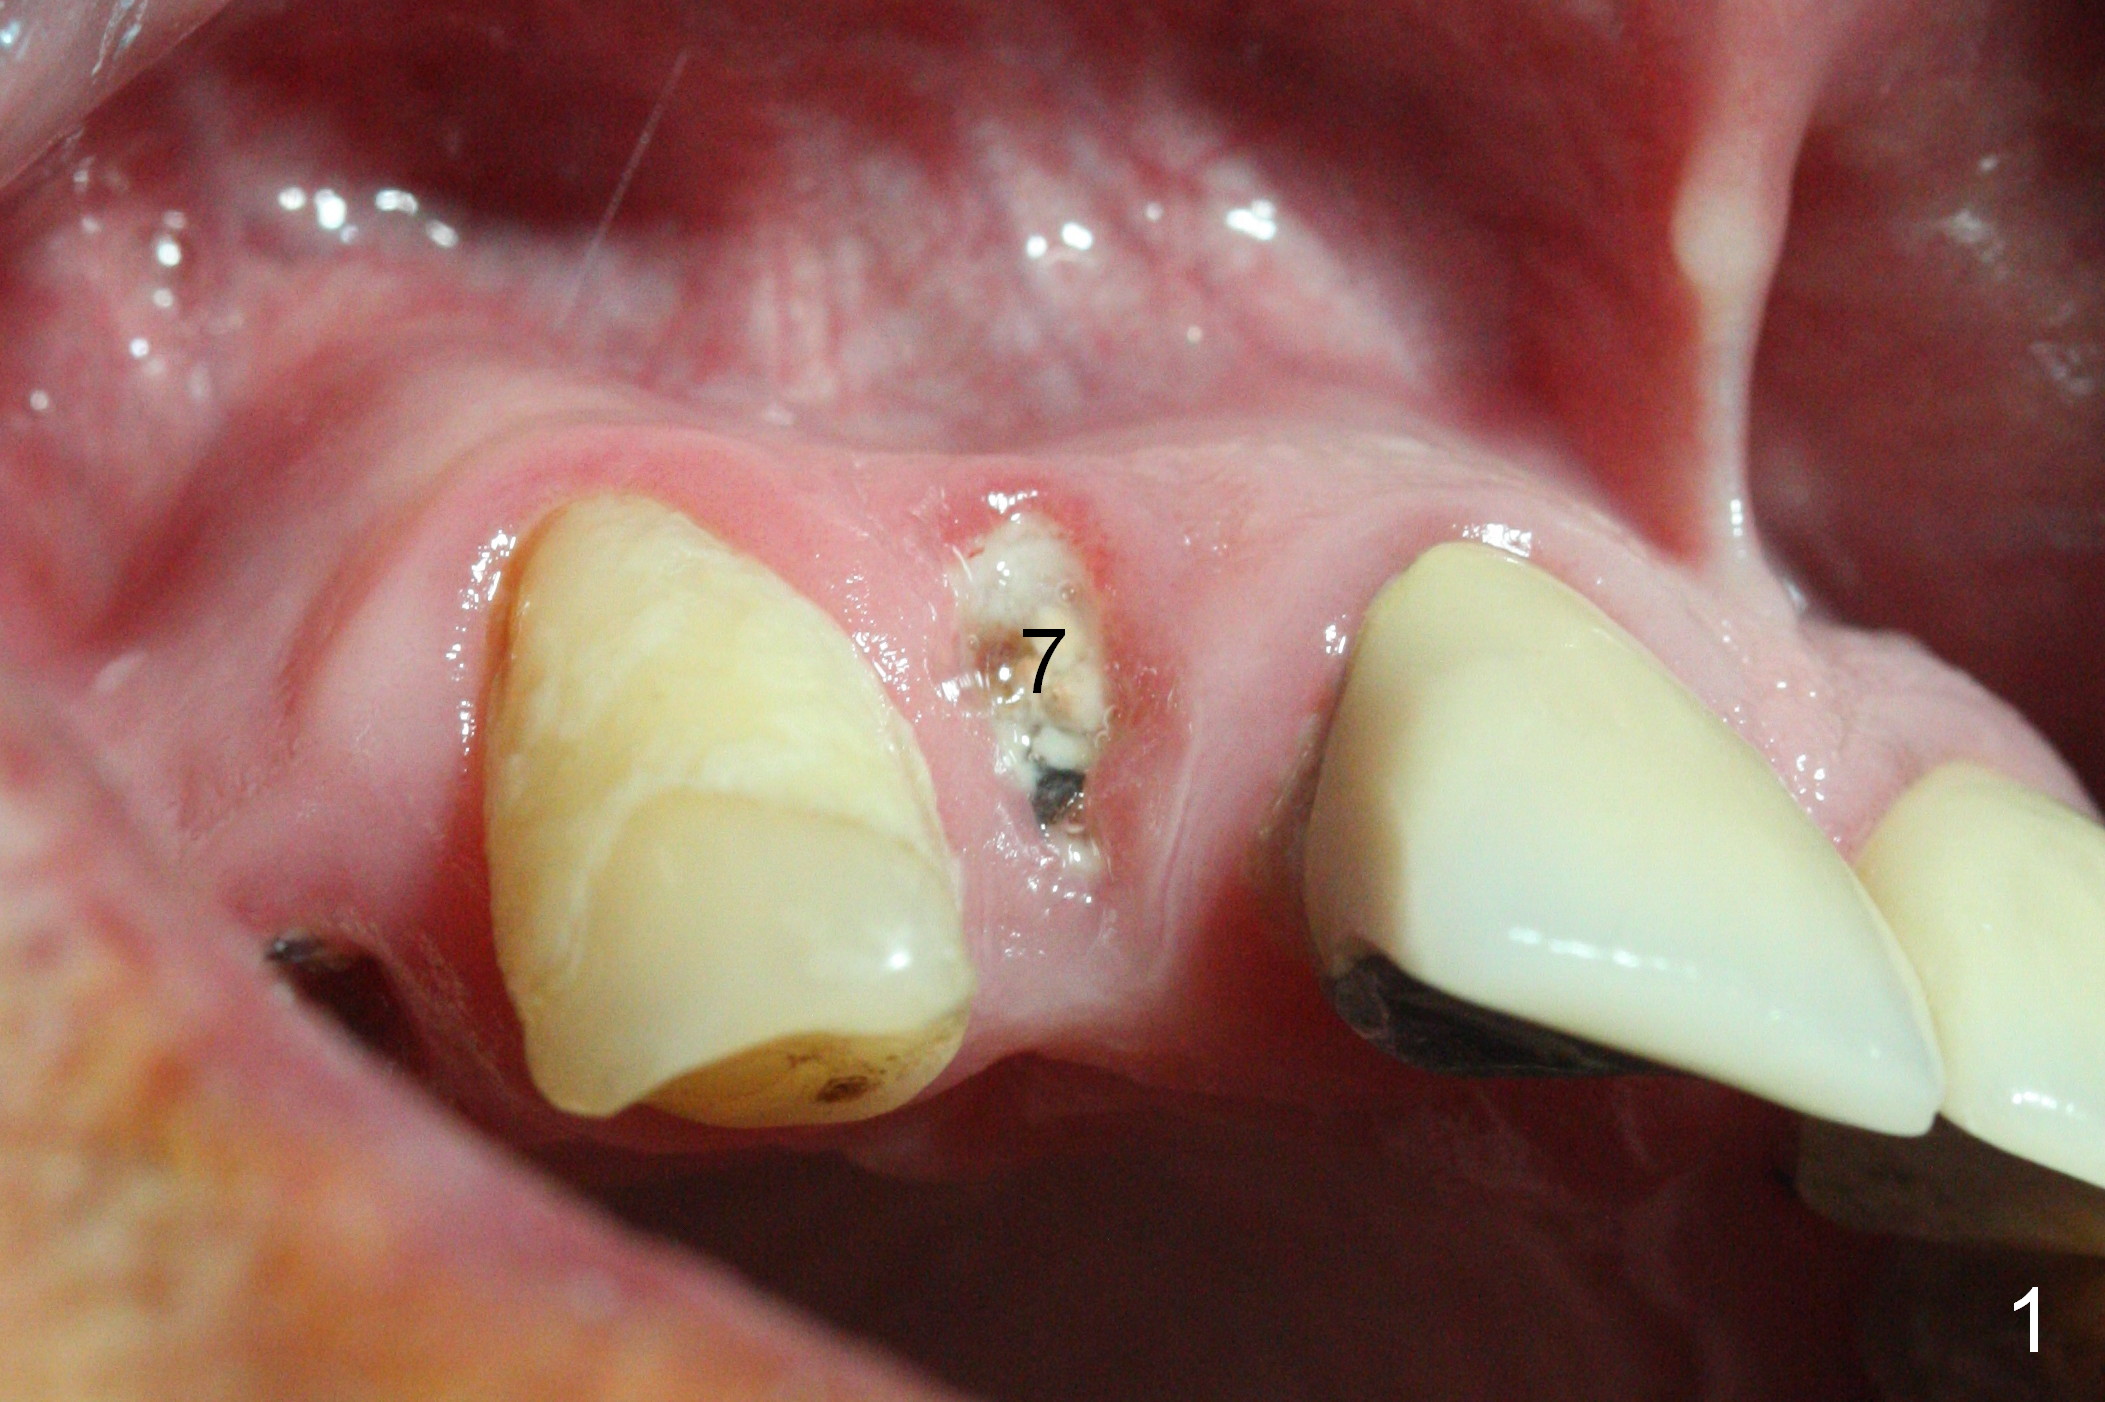

The residual root at #7 is fairly well exposed with buccal gingival recession (Fig.1). The implant placement is flapless (Fig.2-7). What is not shown is that the 3.8x13 mm implant is buccally subcrestally placed (Fig.3). After 1st round of bone graft buccal to the implant, a 4.5x5(5) mm abutment is immediately placed and prepared (Fig.4,5). An immediate provisional is placed after 2nd round of bone graft subgingivally buccally (Fig.6,7). Note the bulging gingiva (*), as compared to that in Fig.4,5. The long implant is chosen because of anterior deep bite (Fig.4) and lack of posterior support (Fig.7).

The gingiva adapts well to the provisional 1 week postop (Fig.8). The buccal gingiva remains recessive and the buccal plate is concave 5.5 months postop (Fig.9-11). It appears that the coronal portion of the buccal plate is resorbed 12 months postop (6 months post cementation, Fig.12 >). Socket shield or smaller diameter implant should have been done to avoid bone loss. Reanalysis of CBCT reveals that implantation apparently increases the bone width and that the buccal plate resorption is not so severe (Fig.13,14 (>: coronal end of the buccal plate)). Panoramic X-ray is taken 2 year 5 month post cementation.